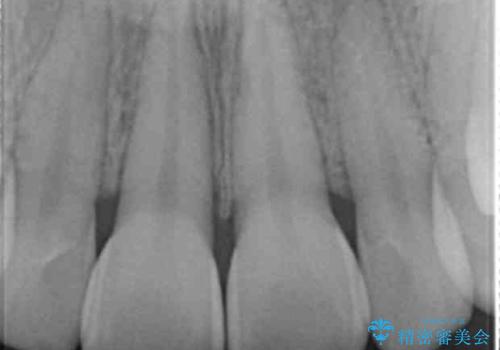

X線検査、歯髄(歯の神経)の検査を行ったところ、失活(歯の神経の死んだ状態)であると診断されました。

放置すると変色が進行するだけでなく、根尖病変も形成される恐れが強いことから、根管治療を行ったのちセラミッククラウンによる審美性の改善を計画します。